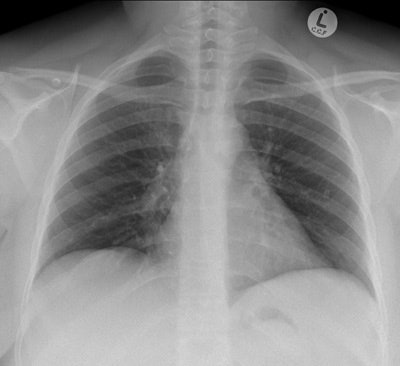

Chest radiograph of a 32-year-old woman shows cardiac migration of the proximal fragment of a fractured portacath. All images courtesy of Drs. Jamal Al Deen Alkoteesh and Maysam T. Abu Sa'a.The portacath fracture was incidentally discovered on chest radiograph, which showed cardiac migration of the proximal fragment. Echocardiography was performed and showed preserved left ventricular function with ejection fraction of about 50% to 55%. No regional wall motion abnormalities seen. Linear shadow was seen on echocardiography, representing the retained fragment.